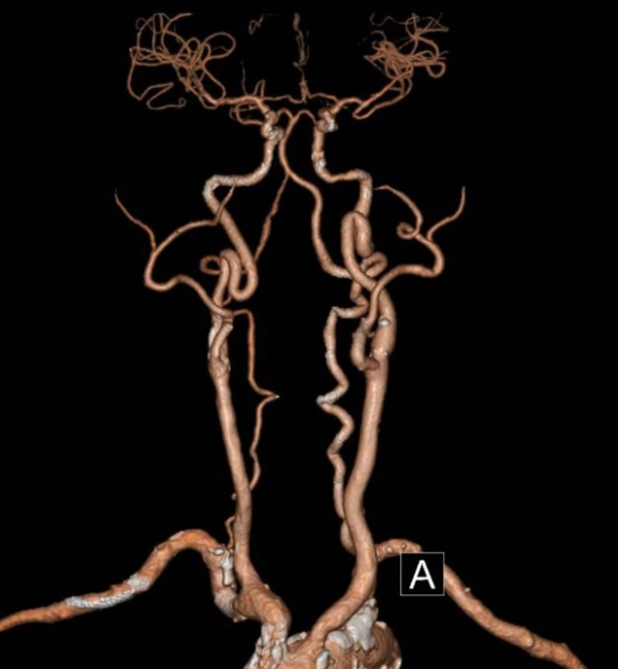

CTA:主动脉及头壁动脉多发斑块,无名动脉起始部支架内重度狭窄。

主动脉弓上造影显示无名动脉起始支架内重度狭窄,右椎动脉显影延迟,解除无名动脉支架内狭窄,恢复血流通畅,同时保障脑保护,降低并发症风险。

无名动脉起始支架内重度狭窄右椎动脉显影延迟